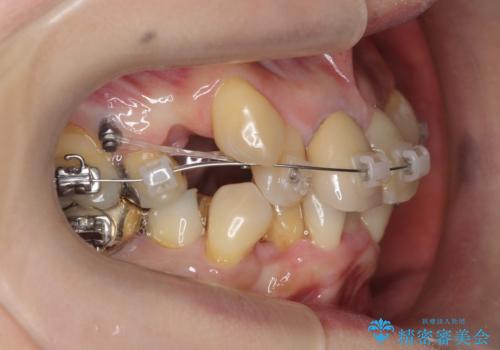

- ワイヤー矯正

- 八重歯の矯正を希望されて来院。

歯は入りきらないため、通常の抜歯矯正を行いました。

歯がご年齢的に動きにくいため、被せ物のやり替えを含めて治療期間の短縮を図りました。

矯正治療自体は2年半、虫歯治療等で1年ほどかかっています。